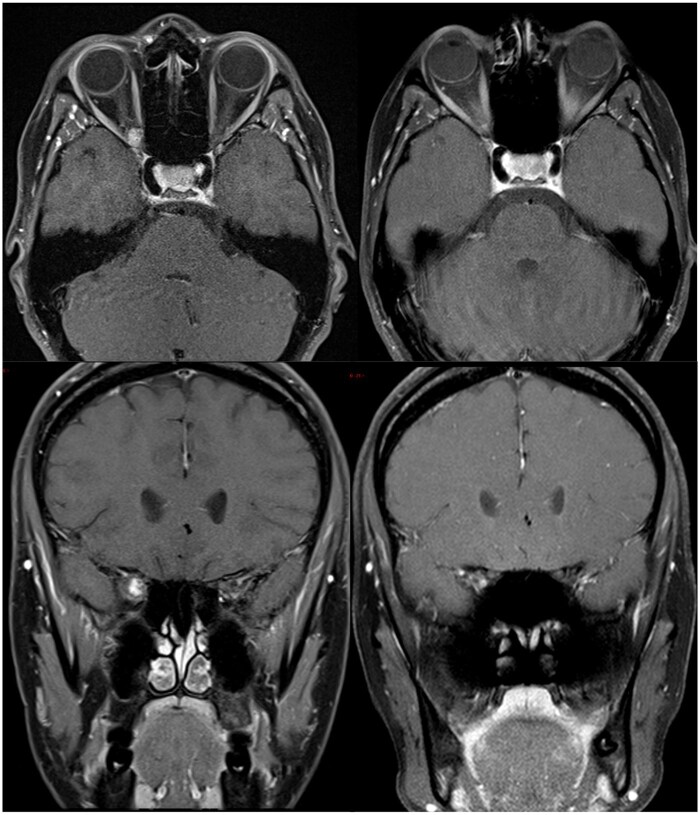

Results: Eight patients were included in our study, six patients with an optic nerve sheath meningioma, one cavernous haemangioma and one orbital schwannoma. All patients demonstrated tumour regression, mean tumour volume prior to treatment of was 4916 mm3 and reduced to 3239 mm3 (P = .03). Three of eight patients showed improvement of visual acuity, three retained excellent pre-treatment vision and two patients had a reduction of vision. HA and VMAT planning target volume coverage dosimetry was similar (D95%: 98.7% and 98.6%, P > .05). The dosimetry of the contralateral lens (32.2 vs 69.8 Gy), lacrimal gland (1.7 vs 7.8 Gy), optic nerve (9.0 vs 26.6 Gy), nasal cavity (10.2 vs 20.6 Gy) and ipsilateral temporal lobe (4.9 vs 11.6 Gy) was significantly improved (P < .001) with HA.

Conclusion: This is the first reported clinical application of HA for benign orbital tumours. HA was an effective and well tolerated treatment modality. HA offered better dosimetry for some of the OARs compared to VMAT.

Advances in knowledge: This is the first article reporting the use of the HA system for planning and delivery of radiotherapy for orbital tumours.